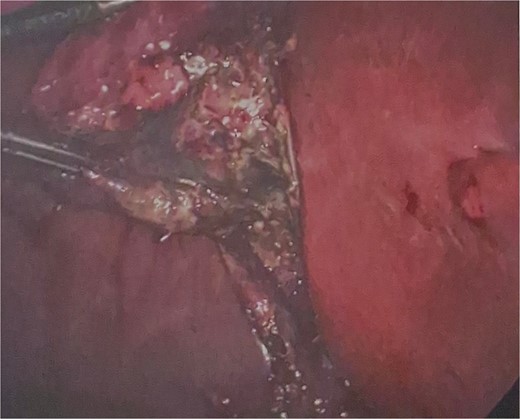

He was brought to theatre for a combined laparoscopic appendicectomy, drainage of peri-appendiceal abscess and cholecystectomy with intraoperative cholangiogram. Intraoperative findings included a 2 cm peri-appendiceal abscess cavity (Fig. 3) in keeping with pre-operative imaging. However, the gallbladder was gangrenous with a possible microperforation sealed by omentum (Fig. 4). Based on the intraoperative appearance, it was difficult to ascertain whether the abscess was due to primary appendicitis or whether the abscess was seeded from the cholecystitis and the appendix had become involved collaterally.

Final histology showed gangrenous cholecystitis with evidence of perforation and a calculus lodged in the gallbladder neck. Appendix histology showed features in keeping with a perforated diverticula at the tip of the appendix with associated active inflammation and no fecalith, suggesting that the two pathologies occurred independently of each other.